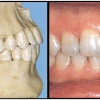

Ülemiste tsentraalsete lõikehammaste (intsisiivide) vahetumine. Retineerunud Intsisiiv

Ülemiste tsentraalsete lõikehammaste (intsisiivide) vahetumine. Retineerunud intsisiivid. Ülemised tsentraalsed esihambad lõikuvad orienteeruvalt 7-8-aastaselt. Enamasti lõikuvad samanimelised jäävhambad paaridena. Normaalne lõikumise järjekord 7, 5-aastselt: vt pilti